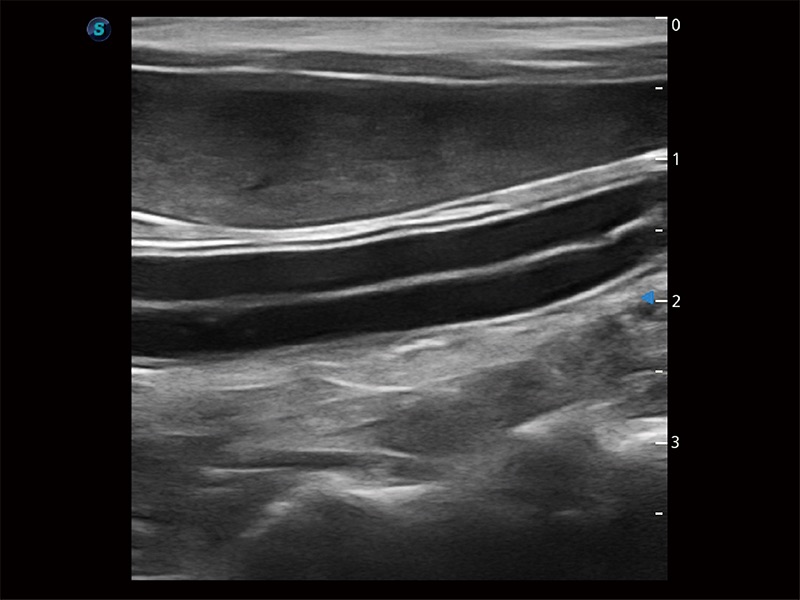

Klinisches Vertrauen verlangt hohe Leistung und fortschrittliche Werkzeuge. ProPet wurde für abdominelle und oberflächliche Untersuchungen mit fortschrittlichen Werkzeugen entwickelt, die Tierärzten in der täglichen klinischen Praxis helfen wie nie zuvor.

ProPet80 vereint die neueste intelligente veterinärmedizinische Software mit der Monokristall-Schallkopftechnologie, um außergewöhnliche Bilder zu liefern, die auch subtilste Veränderungen erkennen lassen - bei Doggen bis hin zu winzigen Exoten - und liefert deutlich bessere klinische Ergebnisse.